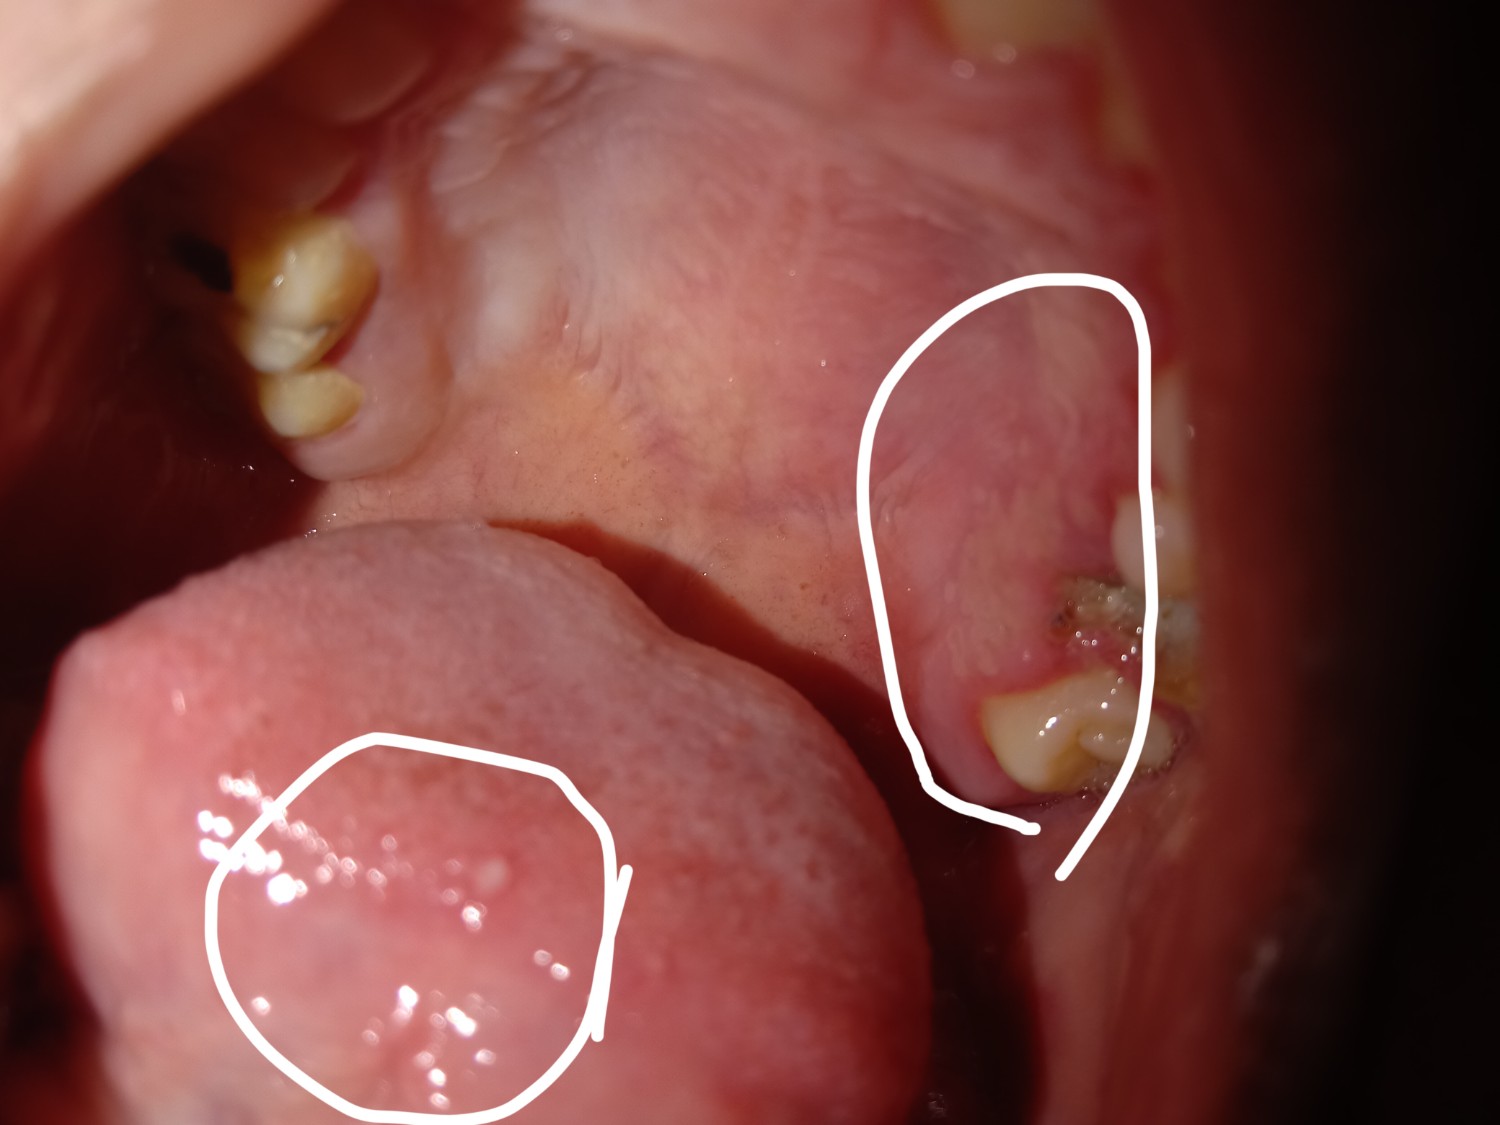

เป็นตุ่มแบบนี้เป็นอะไรคะ